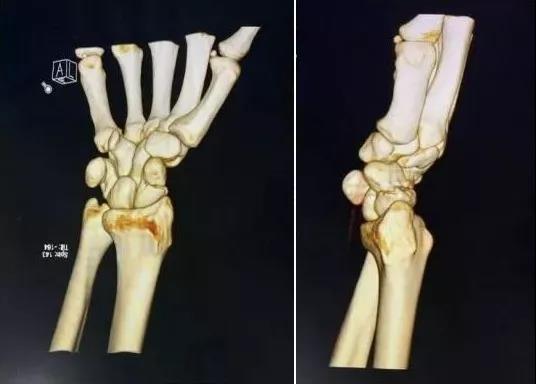

6)桡骨远端骨折

- 绝大部分骨折可以手法复位制动。

- 关节面粉碎,塌陷者应手术。

- 如果伤后拇长伸肌腱卡压,正中神经损伤者,应立即手术。